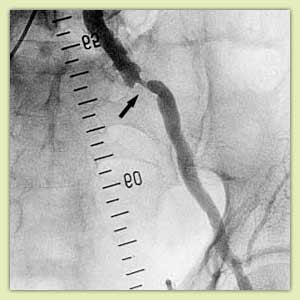

Примеры ангиограмм до и после дилятации:

|

Выраженное сужение наружной подвздошной артерии (стрелка) |

Та же артерия после дилятации баллоном - просвет восстановлен, клинически незначимый остаточный стеноз. |